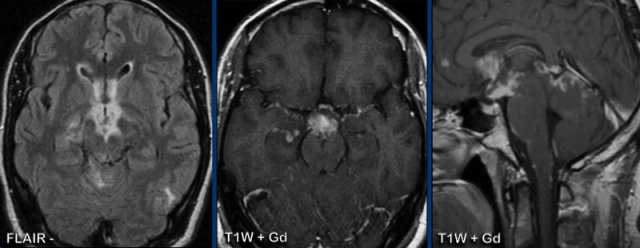

These images are of a 3-year old child who also presented with headache.

There are two important findings.

Take a closer look at the images and then continue reading.

Images

Large cyst with enhancing nodule in the posterior fossa..

Notice that the wall of the cyst enhances.

The nodule is not located on the pial side (inner part of the meninges) unlike in a hemangioblastoma.

Conclusion

Most likely diagnosis at this age is a pilocytic astrocytoma.

The enhancing wall is part of the tumor and needs to be resected.